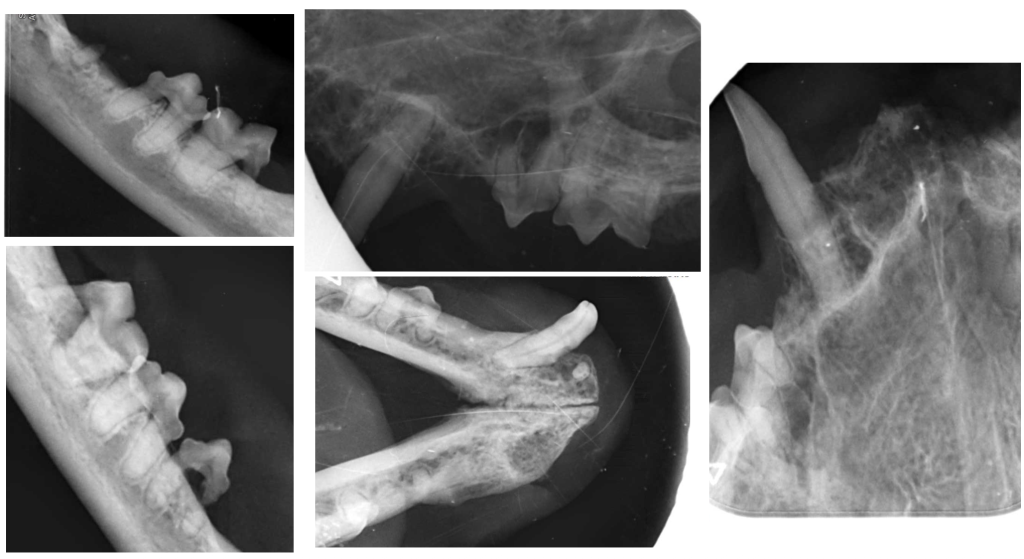

Результат лечения. После операции пациент не демонстрировал симптомов боли, у него улучшился аппетит, появилась прибавка в весе. На контрольных осмотрах наблюдалась положительная динамика состояния слизистой оболочки полости рта (фото 6, 7), поэтому к дополнительным методам лечения не прибегали.

Результат лечения. Спустя 4 месяца контрольный осмотр показал улучшение качества жизни пациента с положительным ответом на хирургическое лечение (фото 12).